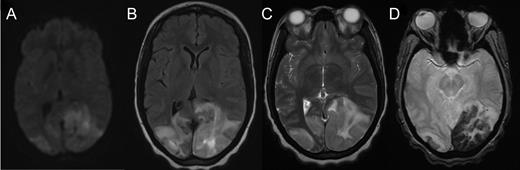

Cranial computed tomography (CT) demonstrated subtle hypodensity mainly in the left occipital lobe, with a characteristic empty delta sign (Fig. 1). Computed tomography angiography demonstrated normal filling of the posterior cerebral arteries (PCA). Cranial magnetic resonance imaging (MRI) evaluations demonstrated bilateral ischemic changes involving the occipital and parietal lobes, more extensively on the left (Fig. 2). Magnetic resonance venography (MRV) demonstrated complete occlusion of the left transverse and sigmoid sinuses, as well as near occlusion of the posterior superior sagittal sinus (Fig. 3C).

Axial MRI demonstrating cerebral tissue injuries from venous hypertension with the associated ischemia: (A) Diffusion-weighted imaging (DWI) MRI. (B) Fluid-attenuated inversion recovery (FLAIR) imaging. (C) T2-weighted MRI. (D) Gradient-echo (GRE) imaging.